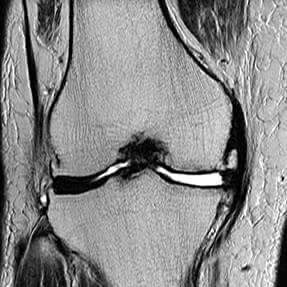

79歳/女性

両ひざのお悩みと診断

- 右は13年ほど前から水がたまり、左は数カ月前から痛みと可動域制限あり。

- ヒアルロン酸注射や電気で改善がなく、ご家族のすすめでご来院。

- 主婦なのに痛みで家事に時間がかかるのがお悩み。

- 右ひざはグレード3(進行期)左ひざは4(末期)と診断。

左ひざの内側には大腿骨・脛骨ともに骨髄浮腫(骨内の炎症)が見られる

右ひざにも骨棘がはっきり確認できる